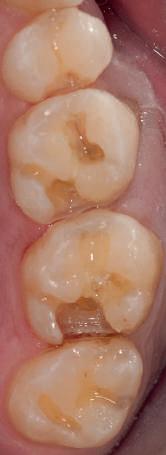

Atitudine: Până la dobândirea vindecării totale a ţesuturilor şi a implanturilor secundare s-au utilizat bonturi standard de titan. Fig. 18 prezintă bonturile individualizate maxilare şi mandibulare aplicate iar fig. 19 un prim-plan al cadranelor de partea dreaptă a pacientului, afişând finalizarea cazului la 15 luni după începerea tratamentului iniţial. Recesiile se pot obiectiva corespunzător 1.4. şi 1.3. În acest caz, s-a încercat minimizarea susceptibilităţii la recesie prin implicarea bonturilor temporare standard fixate cu şurub în cursul fazelor de vindecare pe toată durata etapelor iniţiale ale tratamentului.

Rezultatul final al cazului 5 (fig. 19) prezintă recesie vestibulară de peste 2mm în jurul bonturilor cu sprijin implantar, fiind evidentă prezenţa unui ţesut moale foarte redus din cauza plasării vestibulare a implanturilor. Butler, Kinzer susţin premiza că trebuie să existe suficient volum osos vestibular, chiar şi atunci când implantul este plasat ideal, multe complicaţii fiind legate mai degrabă de poziţia implantului.

Cazul (5):

Bonturi conice utilizate ca bonturi temporare

Figurile

16, 17. Implanturile din prima etapă încărcate cu bonturi conice şi, în unele cazuri, omologii angulaţi.

18. Bonturile individualizate inserate.

19. Rezultat final la 15 luni după începerea tratamentului iniţial.

şi va induce resorbţie osoasă şi migraţia apicală a ţesutului (Saadoun & Touati). Dacă implantul nu este plasat mai palatinal şi la 3-4mm apical de marginea gingivală liberă pentru a asigura profilul de emergenţă adecvat, rezultatul estetic este compromis (Chu et al). Un studiu de 2 ani a demonstrat că implanturile poziţionate anterior au demonstrat o recesie uşor mai accentuată, decât implanturile posterioare (Bengazi et al). Plasarea vestibulară a implanturilor se poate vizualiza clar în cazul 5 (fig. 17) cu bonturile de vindecare în poziţie.

Proximitatea implanturilor adiacente

Se recomandă existenţa a cel puţin 3mm de os între două implanturi adiacente (Tarnow et al). În acelaşi caz 5, corespunzător 2.5. şi 2.6. distanţa la nivel inter-implantar este sub 2mm iar între bonturi sub 1mm (fig. 17). Întrucât ţesuturile inter-implantare nu au acelaşi nivel de suport ca în cazul dinţilor naturali, distanţa interdentară devine esenţială în anticiparea poziţiilor finale ale ţesutului moale.